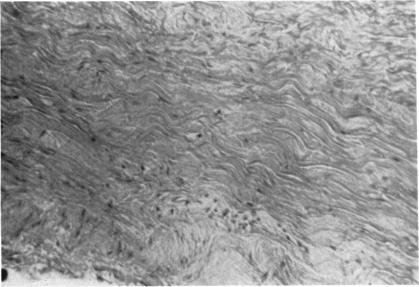

Physiopathologic aspects of scleral stress-strain.

Trans Am Ophthalmol Soc. 1969;67:417-61.